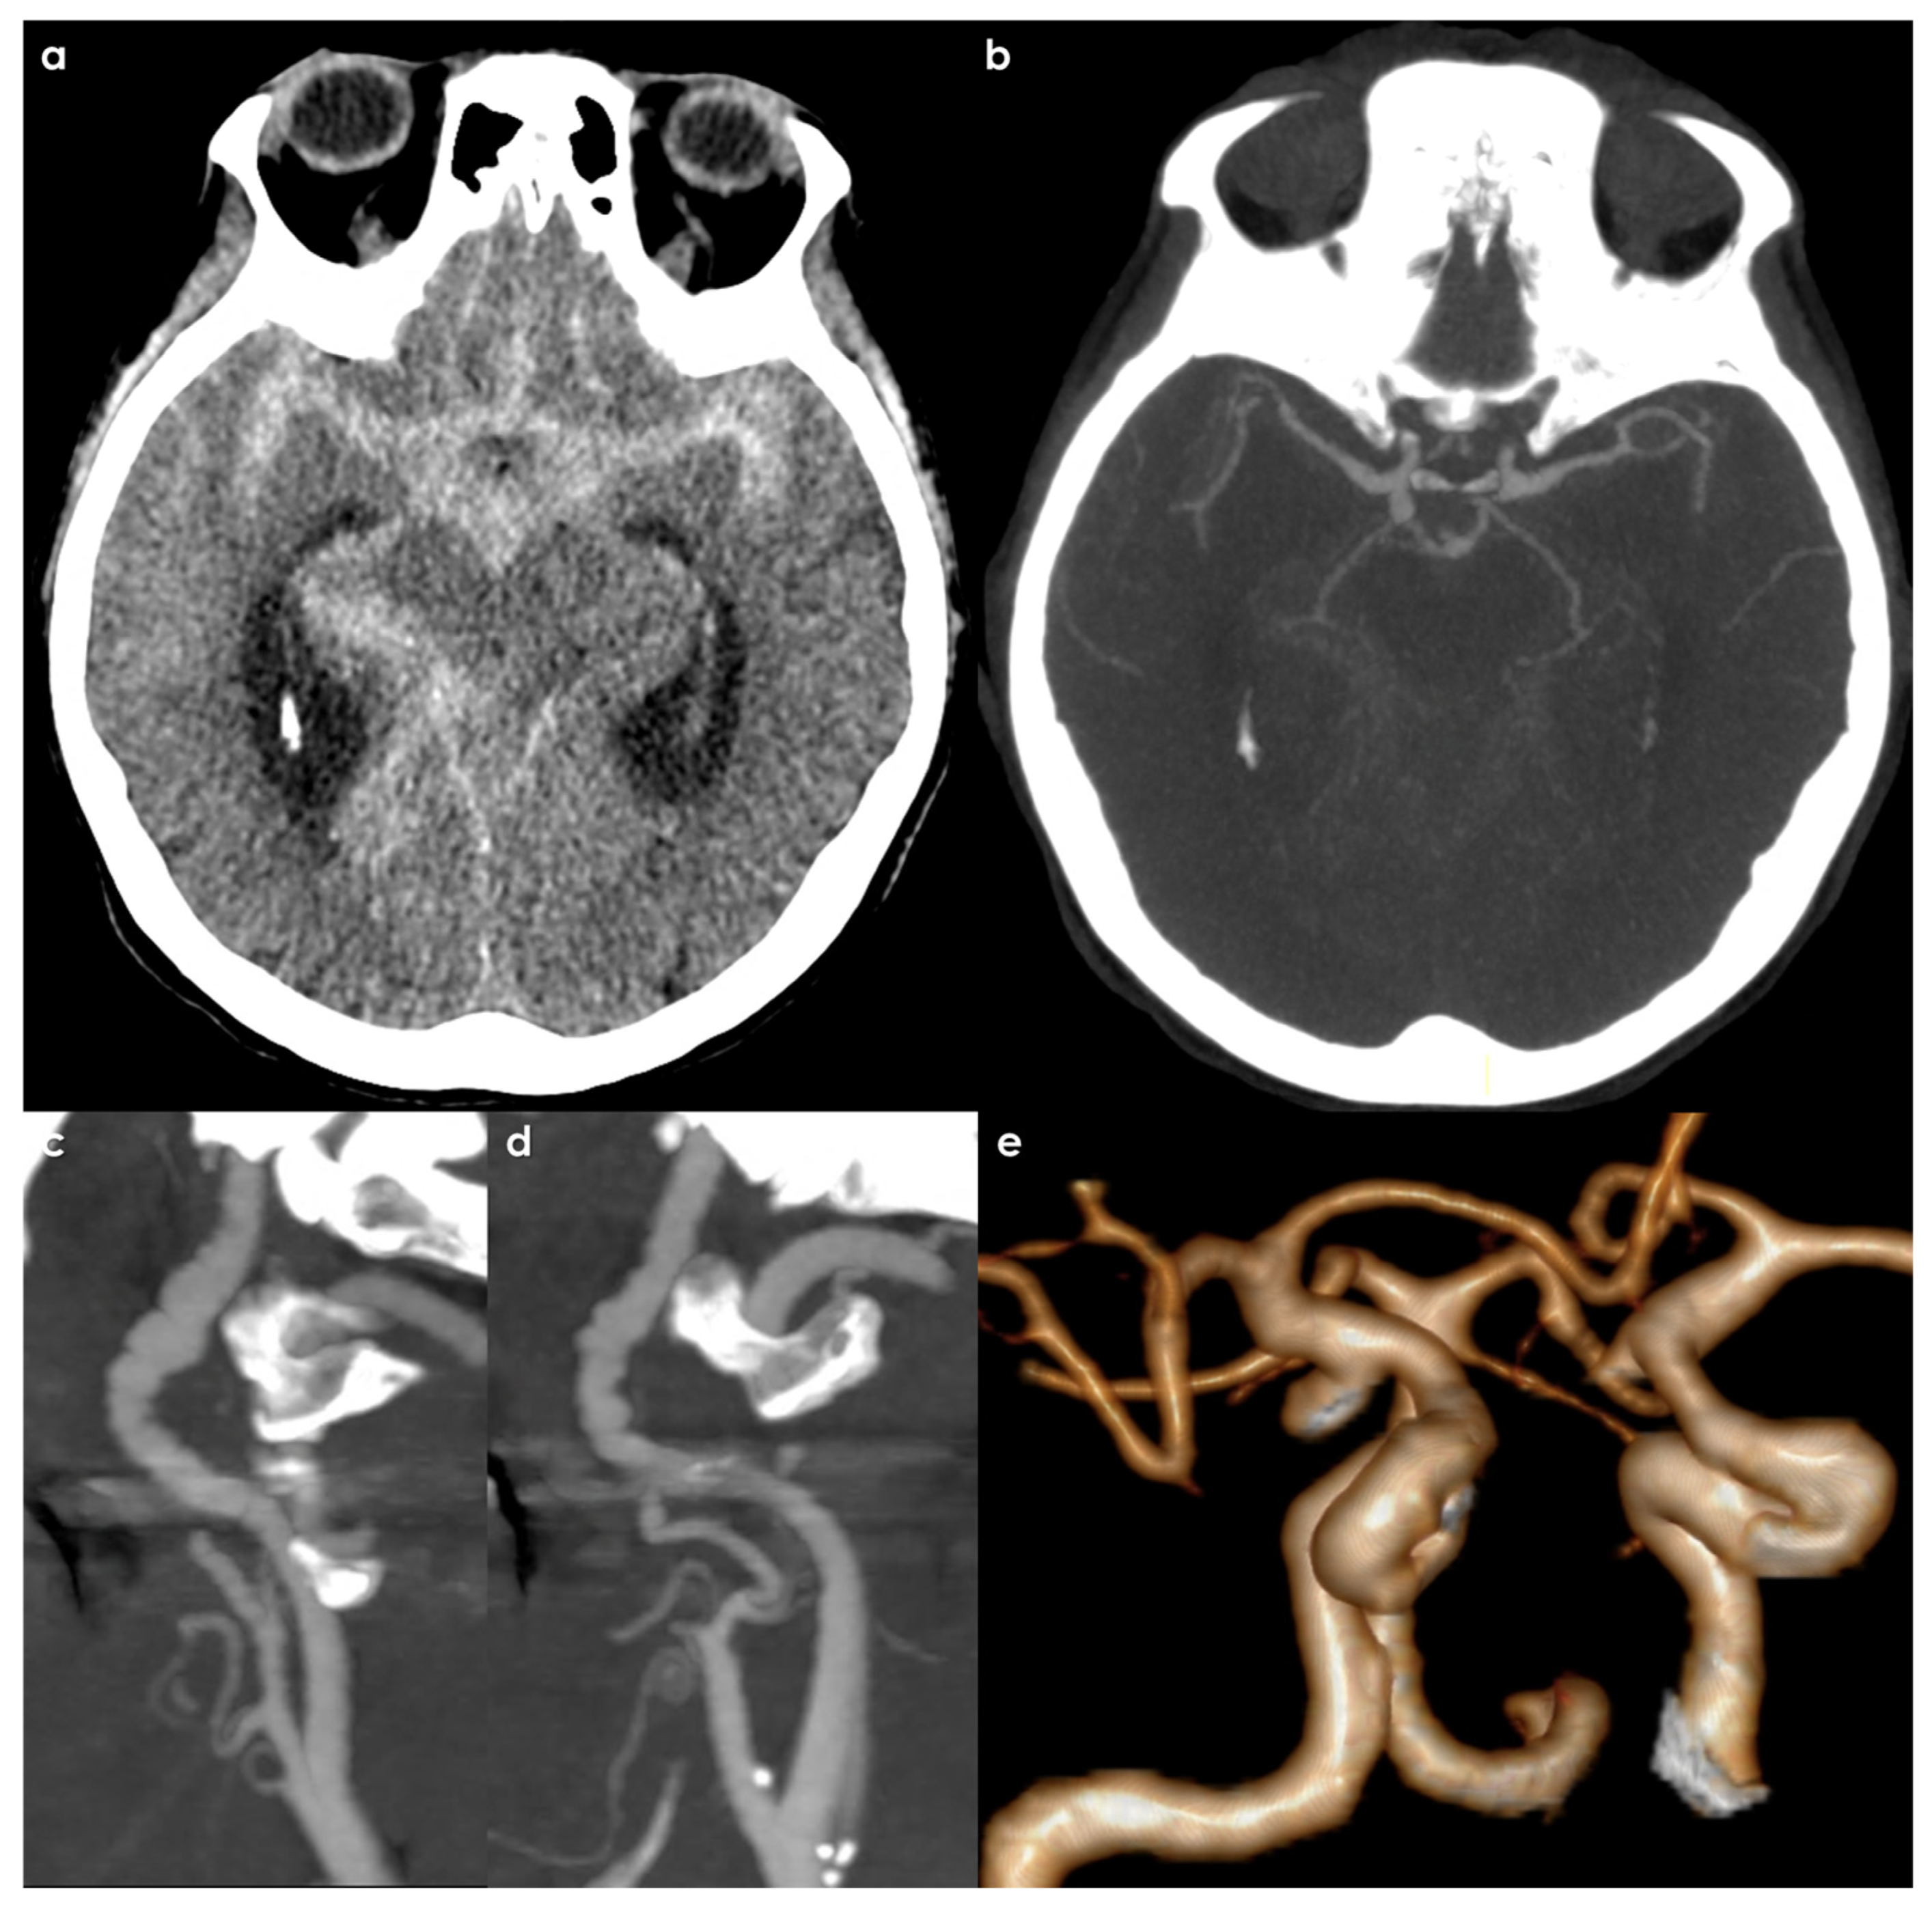

2. Materials and Methods

3. Results

3.3. Features of Intracranial Aneurysms

- Size of Aneurysms: 56/128 (43.2%) aneurysms were ≥5 mm, i.e., at high risk of rupture, illustrating a higher risk profile compared to general population findings. The sizes were categorized as in Figure 1.

- Location of Aneurysms: The distribution of IAs was notable, with a significant number located in areas typically associated with higher risks of rupture. A substantial 41% of the identified intracranial aneurysms were located in the intradural segments of the ICA, which is considered a high-risk area, along with 12% in the posterior communicating artery and 9% in posterior circulation arteries.

- Multiplicity: Many patients presented with multiple IAs, indicating a possible underlying susceptibility linked to the pathophysiology of FMD. The median number of aneurysms per patient was 1, but some had as many as 8 intracranial aneurysms.

3.4. Treatment Issues